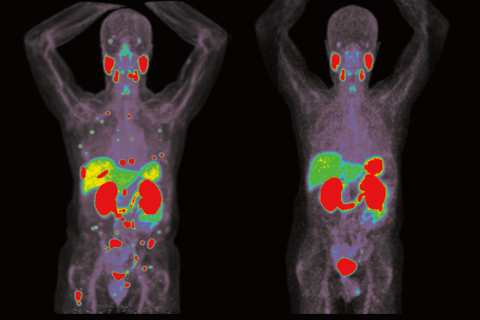

Dr. Johannes Czernin and his colleagues are studying the metabolic phenotype of tumor tissue and its relationship to the genotype.

The focus of Czernin's research is to refine the clinical role of molecular PET imaging. He has adopted a translational research approach by which radioactive ligand uptake in cell cultures determines the use of specific molecular imaging probes in small animals and later on in humans.